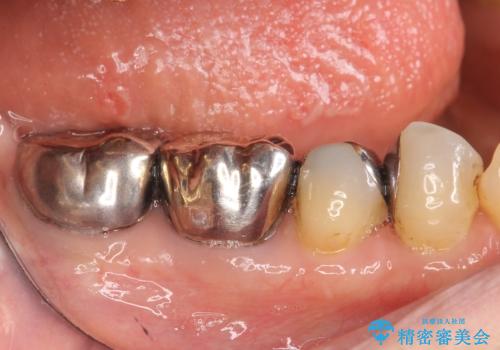

- 右下の古い銀歯のやり替えを希望された方の症例です。

口腔外から見えやすい 4 番目、5 番目の歯はセラミックによる審美的な治療を行い、6 番目、 7 番目の奥歯 2 歯は適合性に優れたPGA(ゴールド)クラウンによる治療を行いました。